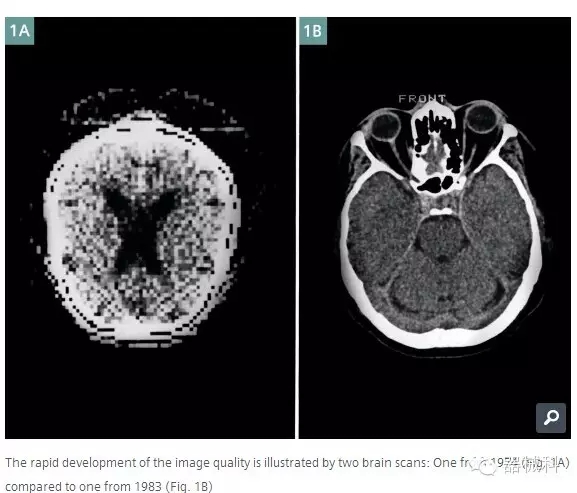

1974年的腦部圖像到了1983年圖像清晰度已經(jīng)有了本質(zhì)的提升